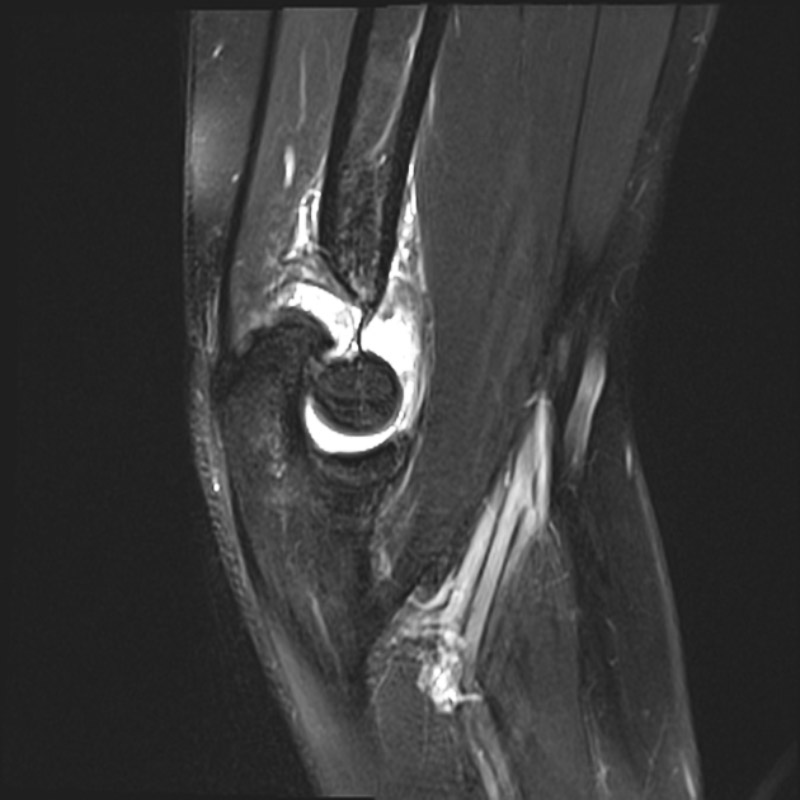

Chụp cộng hưởng từ (MRI) sử dụng từ trường và sóng vô tuyến do máy tính tạo ra để phác họa hình ảnh chi tiết về các cơ quan, mô trong cơ thể. Máy MRI được minh họa như một khối nam châm lớn. Khi người bệnh nằm bên trong, từ trường hoạt động với sóng vô tuyến và các nguyên tử hydro của cơ thể để tạo ra hình ảnh mặt cắt ngang.

Chụp MRI có thể được sử dụng để chẩn đoán các vấn đề về khớp, gồm: